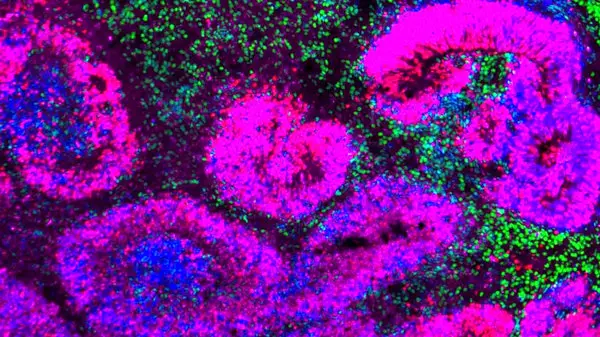

بافت مغز در حال توسعه انسان که شامل ساختارهای رُزت (صورتی و آبی) است و اطراف آن با نورون‌ها (سبز) احاطه شده‌اند.

نانو و همکاران / Nature Neurosci.; خوزه سوتو / آزمایشگاه بهادوری / UCLA